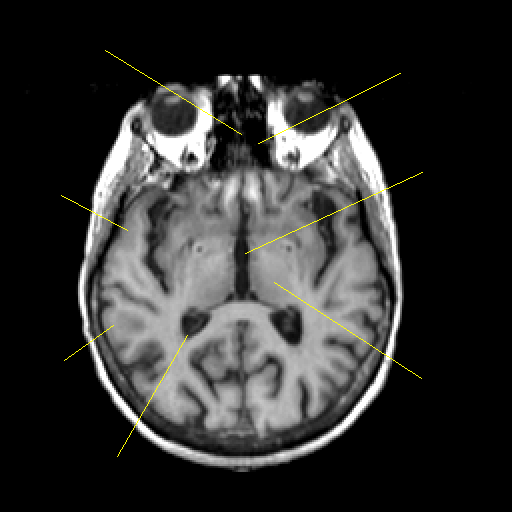

T1-weighted structural MR: Slice 26

Slice 26

Pointers

Labeled